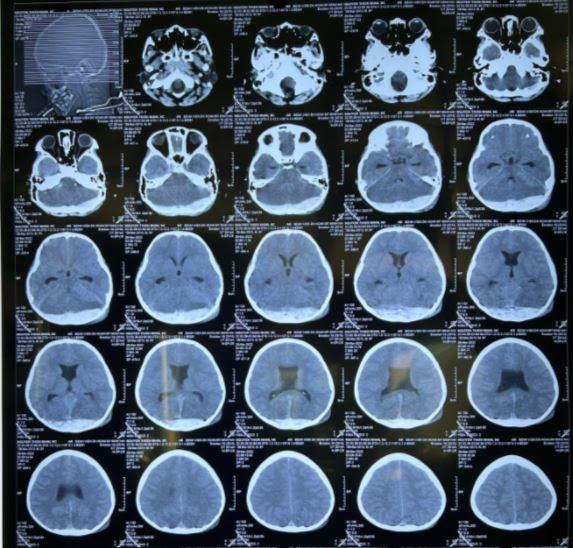

Hình ảnh máu tụ rất nhiều tại vùng chẩm (sau gáy) của bệnh nhi 8 tuổi

Trường hợp cháu bé 8 tuổi bị tai nạn nêu trên, sau gáy bị sưng to. Tại địa phương cháu được đi khám bác sĩ tư, nhưng bác sĩ không phát hiện ra có tổn thương não bên trong, chỉ cho uống thuốc giảm sưng đau thông thường. Sáng hôm sau, cha mẹ phát hiện bé bị hôn mê, đưa đi bệnh viện cấp cứu nhưng đã muộn, cháu bé đã ngưng tim.